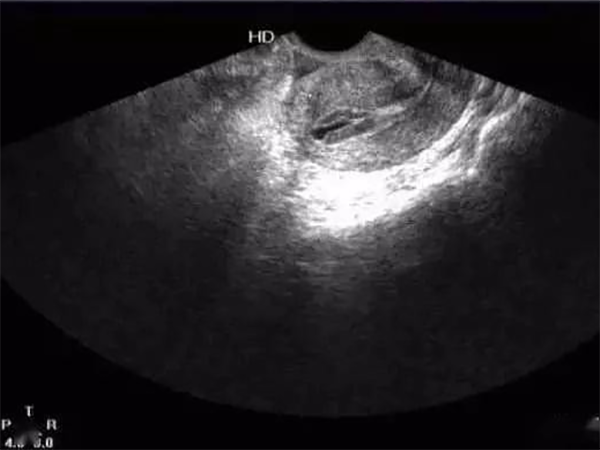

打夜针并取卵后的当天仅有5是否会有增厚的情况?

日野香穗子

对于试管周期中的女性来讲,在打完夜针、取完卵之后即使内膜只有5mm,也还是会继续长厚的,因为取卵不会...